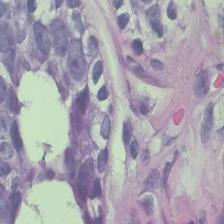

We present a novel technique to discover and exploit weak causal signals directly from images via neural networks for classification purposes. This way, we model how the presence of a feature in one part of the image affects the appearance of another feature in a different part of the image. Our method consists of a convolutional neural network backbone and a causality-factors extractor module, which computes weights to enhance each feature map according to its causal influence in the scene. We developed different architecture variants and empirically evaluated all of our models on two public datasets of prostate MRI images and breast histopathology slides for cancer diagnosis. To confirm our quantitative results, we conduct ablation studies and investigate the explainability of our models via class activation maps. Our findings show that our lightweight block extracts meaningful information and improves the overall classification, together with producing more robust predictions that focus on relevant parts of the image. That is crucial in medical imaging, where accurate and reliable classifications are essential for effective diagnosis and treatment planning.